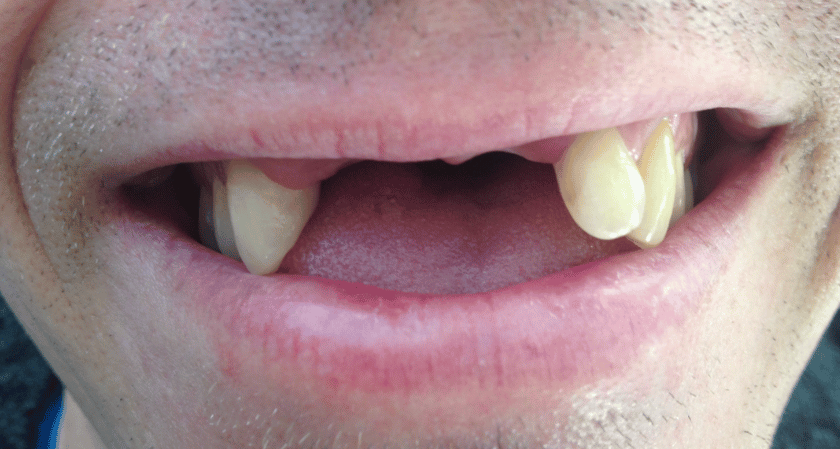

LEARN MORECase 22

This patient had a combination of implants for her missing teeth and crowns for the existing teeth.